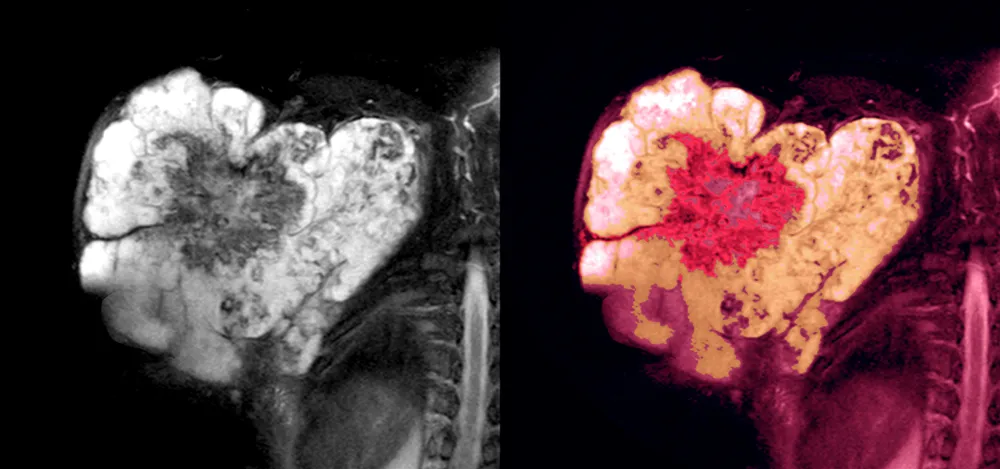

Soft Tissue Sarcoma Treatment at Apollo Hyderabad

State-of-the-art facilities for Soft Tissue Sarcoma treatment in Hyderabad at Apollo Cancer Centres, Jubilee Hills, Hyderabad.

Latest PET-CT and MRI scans for accurate staging.